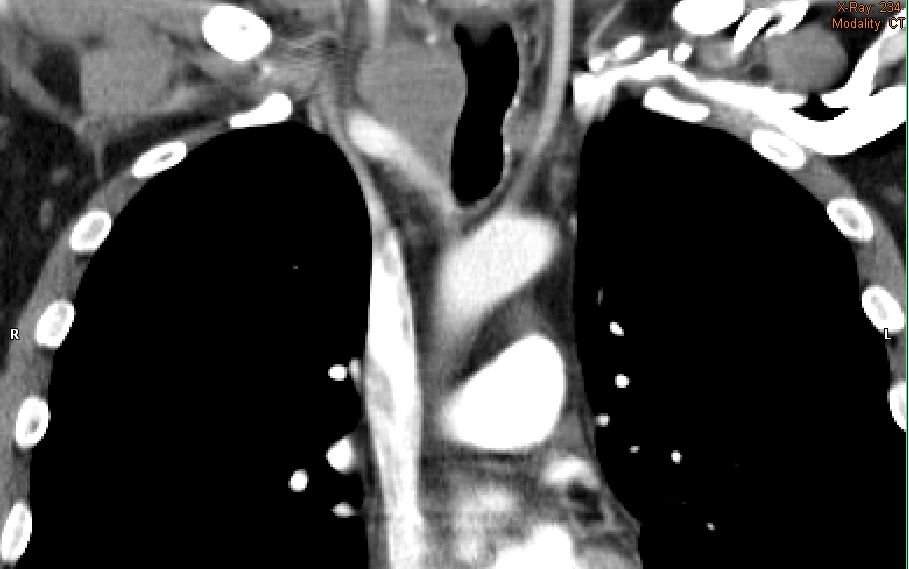

Rezidiv nach Radiochemotherapie eines kleinzelligen Tracheakarzinoms mit großer supraclavikulärer Metastase | |||